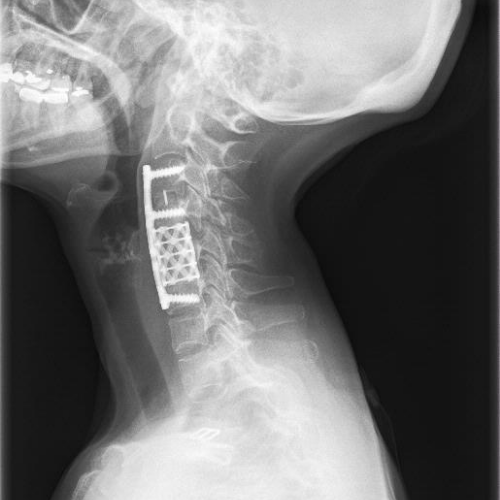

Disk Hernileri (Fıtıklar) Boyun (servikal), bel (lomber) veya daha nadir görülen sırt (torakal) fıtığı, travma, ağır kaldırma, fazla kilo, yaşlılık, postür bozukluğu, genetik yatkınlık gibi çeşitli nedenlere bağlı olarak omurga kemikleri arasında bulunan disk adı verilen yapıların neden olduğu hastalıktır. Az önce saydığımız nedenlere bağlı olarak diskin çevresini oluşturan annulus yapısının yıpranmasını takiben diskin ortasında […]

Spondilolistezis (Omurga Kayması) Spondilolistezis veya Türkçe adı ile omurga kayması çeşitli nedenlere bağlı olarak, üst üste hizalı dizilimde olan omurgaların bir veya daha fazlasının bu hizalı dizilimi bozacak şekilde yer değiştirmesi yani kaymasıdır. Bu kayma genellikle öne doğru olabileceği gibi arkaya, sağa veya sola olmak üzere her yöne doğru olabilir. Kayma boyun, sırt ve bel […]

Spinal Stenoz (Omurga Kanalı Darlığı) Omurga kanalı darlığı çoğunlukla yaşlanmaya bağlı dejeneratif değişikler sonrası oluşur ve omuriliği baskıya uğratır. Yaşlanma ile diskin su içeriği azalır, disk yüksekliği azalır ve omurgalar arasındaki disk aralığı daralır. Disk esnekliğini kaybederek omurgaya gelen darbeleri emme görevini yapamaz. Aynı zamanda ligaman denilen omurga kemiklerini birbirine bağlayan esnek yapılar kalınlaşır ve […]